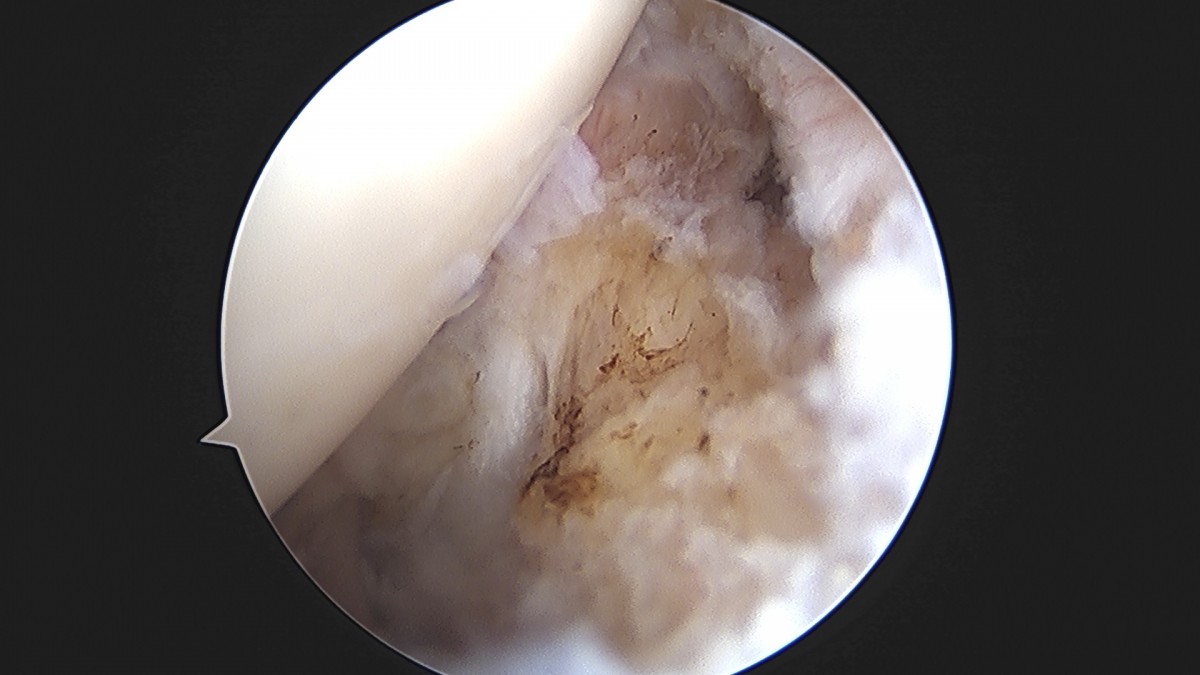

이재상원장님 어깨 견봉하 감압술 및 관절낭 이완술 주혜O 환자

dae765e4d9ac96aee867c9d6292d8784_1758003912_2111.jpg